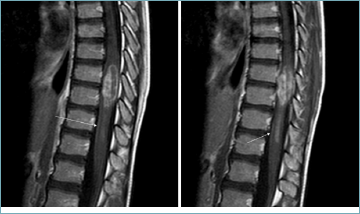

Case 2 had an institutional and centralized diagnosis of spinal cord low-grade glioma NOS. The tumor was subsequently classified as diffuse leptomeningeal glioneuronal tumor, subtype 1, accordingly to the methylation profile. Preoperative MRI revealed an intramedullary lesion with impregnation of the meninges after contrast medium (Fig. 2). At the microscopic evaluation the tumor was composed of monomorphic, medium sized cells with roundish nuclei and eosinophilic cytoplasm (Fig. 1b). Diffuse leptomeningeal glioneuronal tumor was included in the 2016 WHO classification of CNS tumors 16, although already addressed in previous years under various names 19. The term “diffuse glioneuronal leptomeningeal tumor” was first used by Gardiman 2010 20. A characteristic radiological feature of this tumor is a widespread diffuse leptomeningeal enhancement with or without association to intraparenchymal lesions. The most typical histological feature is the monomorphic, oligodendrocyte-like “fried egg” morphology of the tumor cells, marked by regular round nuclei and abundant clear cytoplasm. From a molecular standpoint, this entity is characterized by 1p loss, a less frequent loss of chromosome 19q, and a gain of 1q, along with mitogen-activated protein kinase (MAPK) pathway gene alterations (most commonly KIAA1549::BRAF fusions). In cases of 1p/19q co-deletion, the differential diagnosis with oligodendroglioma, which also exhibits 1p/19q co-deletion, can be established based on the presence or absence of IDH1/IDH2 mutations. These mutations are indeed present in oligodendroglioma but absent in diffuse leptomeningeal glioneuronal tumors 21. The WHO classifies this tumor as a relatively indolent, grade 2 lesions in most cases 21. However, a less favorable behavior has been described particularly in cases with 1q gain, leading to the assignment of grade 3 to these tumors 19,21. Our tumor was 1p-19q co-deleted without 1q gain (Fig. 3a). This case suggests that the possible diagnosis of diffuse leptomeningeal glioneuronal tumor should be considered in the presence of suggestive imaging, even when morphology is not prototypical. Indeed, it has been reported that this tumor can exhibit a wide spectrum of morphological features, with many cases identified only through methylation profiling 6. In the case presented, it should be considered that it dates to the year preceding the inclusion of this tumor entity in the 2016 WHO classification of CNS tumors 16.

Figure 2. Contiguous sagittal post-contrast T1-weightedimages demonstrating intramedullary lesion at D9 and D10, with inhomogeneous contrast enhancement. Linear enhancement along the anterior aspect of the cord (arrows) is consistent with leptomeningeal infiltration.